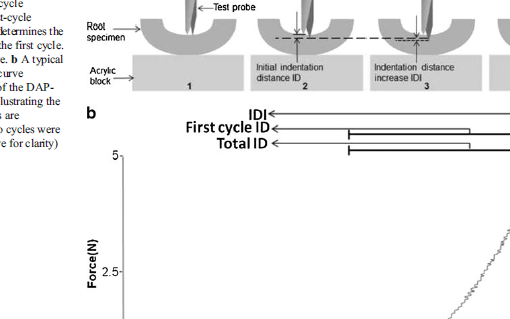

Densitometry and imaging techniques are currently used in clinical settings to measure bone quantity and spatial structure. Recently, Reference Point Indentation has opened the possibility of directly assessing the mechanical characteristics of cortical bone in living individuals, adding a new dimension to the assessment of bone strength. Impact microindentation was specifically developed for clinical studies and has been tested in several populations where there are discrepancies between bone density and fracture propensity, such as type 2 diabetes, atypical femoral fracture, stress fractures, glucocorticoid treatment, patients with osteopenia and fragility fractures, and individuals infected with HIV, among others. Microindentation will complement, not replace, existing bone analysis methods, particularly where bone mineral density does not fully explain fracture propensity. The available evidence provides solid proof of concept; future studies will fully define the role of microindentation for the assessment of bone health both in clinics and in research.